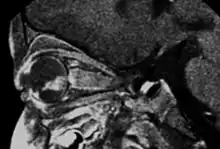

Aspect of trilateral retinoblastoma on MRI

Inherited forms of retinoblastomas are more likely to be bilateral. In addition, inherited uni- or bilateral retinoblastomas may be associated with pineoblastoma and other malignant midline supratentorial primitive neuroectodermal tumors (PNETs) with a dismal outcome; retinoblastoma concurrent with a PNET is known as trilateral retinoblastoma.[15] A 2014 meta-analysis showed that 5-year survival of trilateral retinoblastoma increased from 6% before 1995 to 57% by 2014, attributed to early detection and improved chemotherapy.[16]

In about two-thirds of cases,[27] only one eye is affected (unilateral retinoblastoma); in the other third, tumors develop in both eyes (bilateral retinoblastoma). The number and size of tumors on each eye may vary. In certain cases, the pineal gland or the suprasellar or parasellar region (or in very rare cases other midline intracranial locations) is also affected (trilateral retinoblastoma). The position, size, and quantity of tumors are considered when choosing the type of treatment for the disease.

Traditional ultrasound B scan can detect calcifications in the tumour while high-frequency ultrasound B scan is able to provide higher resolution than the traditional ultrasound and determine the proximity of the tumour with front portion of the eye. MRI scan can detect high-risk features such as optic nerve invasion; choroidal invasion, scleral invasion, and intracranial invasion. CT scan is generally avoided because radiation can stimulate the formation of more eye tumours in those with RB1 genetic mutation.[35]